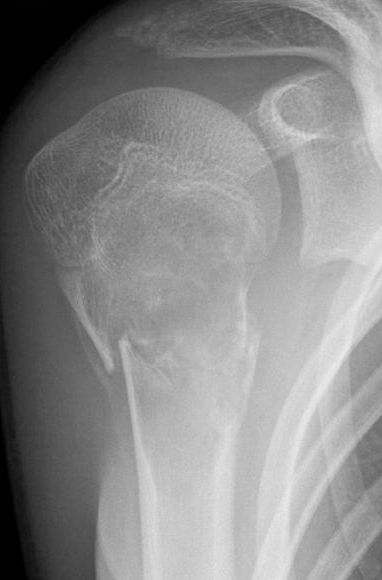

Basit kemik kistleri büyüyen çocuklarda en sık görülen kanser dışı kemik lezyonu. Kistler kemik korteksini inceltir ve tekrarlayan patolojik kırıklara neden olabilir. Bu kırıklar bazen ekstremitede kısalma ve şekil bozukluğuna yol açar. Basit kemik kistlerinin tedavisinde ana hedef patolojik kırık riskini azaltmak, kistin iyileşmesine yardım etmek ve ağrıyı gidermektir. Halen mevcut birkaç tedavi yöntemi var ancak hangisinin en iyisi olduğu konusunda anlaşma bulunmuyor. Bu yüzden tedavideki en iyi metodu belirlemek amacıyla mevcut kanıtları kapsamlı olarak araştırdık. Bu derleme 2014 yılında yayınlanan versiyonun güncellemesi.

77 çocuğa ait sonuçlar sağlanabildi. Tedaviden 2 yıl sonraki röntgen filminde; steroid enjeksiyonu yapılan çocuklarda başarılı iyileşmenin daha sık olduğunu gösterdi; ancak bunun doğru bir bulgu olduğundan çok şüpheliyiz. Düşük kalitede kanıtlar tedaviden iki yıl sonra iki tedavi grubunda da benzer şekilde yüksek düzeyde fonksiyon (Çocuklar İçin Aktivite Skoru ile ölçüldü) ve daha az ağrı (Oucher skoruyla ölçüldü) gösterdi.